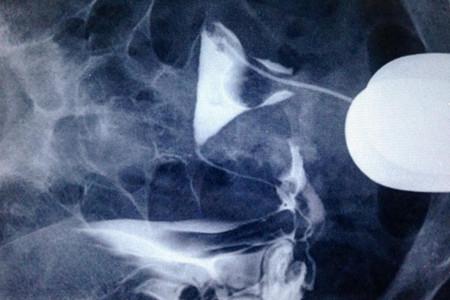

输卵管通水有时候是能够把轻微堵塞的输卵管通开的,因为有的输卵管堵塞是由于输卵管内有黏液,或者有少量的子宫内膜的组织堵塞引起的,如果用通水的方法,就可以将这些物质疏通开,但是如果是输卵管粘连并且粘连比较严重,用通水的方法也是通不开的。需要做输卵管检查,最好是做输卵管造影,可以在X光的照射下直接能够看到输卵管是否通畅的,单纯的用通水的方法是不能确定输卵管是否通开。

输卵管方面的因素是导致女性不孕的最常见原因之一,做输卵管通水主要是为了解决输卵管不通导致的不孕的问题,但输卵管手术属于盲通,术者也不知道哪侧输卵管通,哪侧不通,也不确定具体是什么位置不通,多次进行输卵管通水手术还面临着感染的可能,所以现在临床上多采用输卵管造影手术代替输卵管通水手术,可以检查明确输卵管具体的堵塞位置之后进行针对性治疗。

输卵管堵塞的治疗首先要确诊存在输卵管阻塞,比如输卵管通液,输卵管碘油造影,输卵管碘油造影B超引导下的检查,包括宫腹腔镜检查,确定是否存在输卵管堵塞。